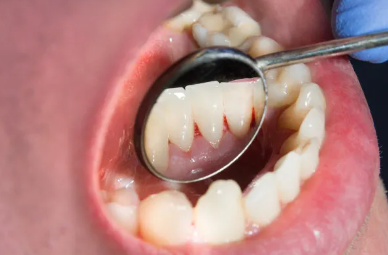

5、增加其他牙齿负担

牙齿承受的咀嚼力是有一定限度的,当个别牙齿缺失后,咀嚼力集中在余留的牙齿上,对余留牙齿造成创伤而产生牙周疾患。如果长时间没有镶牙,可能导致其相邻的真牙向这个缺牙空隙内倾斜、移位,最后出现松动和缺失的情况。